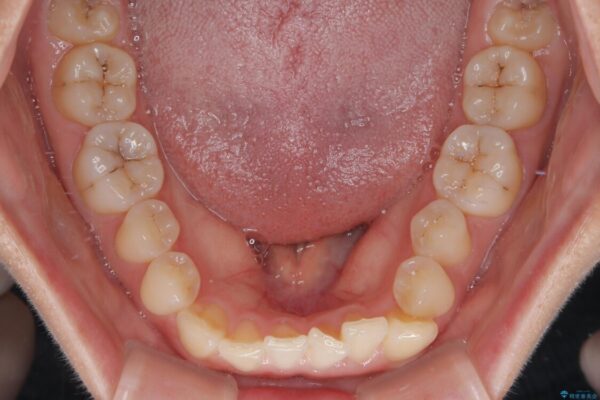

診察の結果、上下の前歯部に**叢生(そうせい/歯のガタガタ・重なり)**が認められました。

特に上の前歯にはねじれや重なりがあり、審美的にも清掃性にも影響している状態でした。

また、上顎前歯の重なっていた部分にはむし歯が見つかり、治療中に適切な処置を行っています。

治療前

• 前歯のねじれ・ガタガタを10か月で改善!20代女性の矯正治療|クリアブラケットでむし歯になりにくい歯並びへ改善 治療前画像